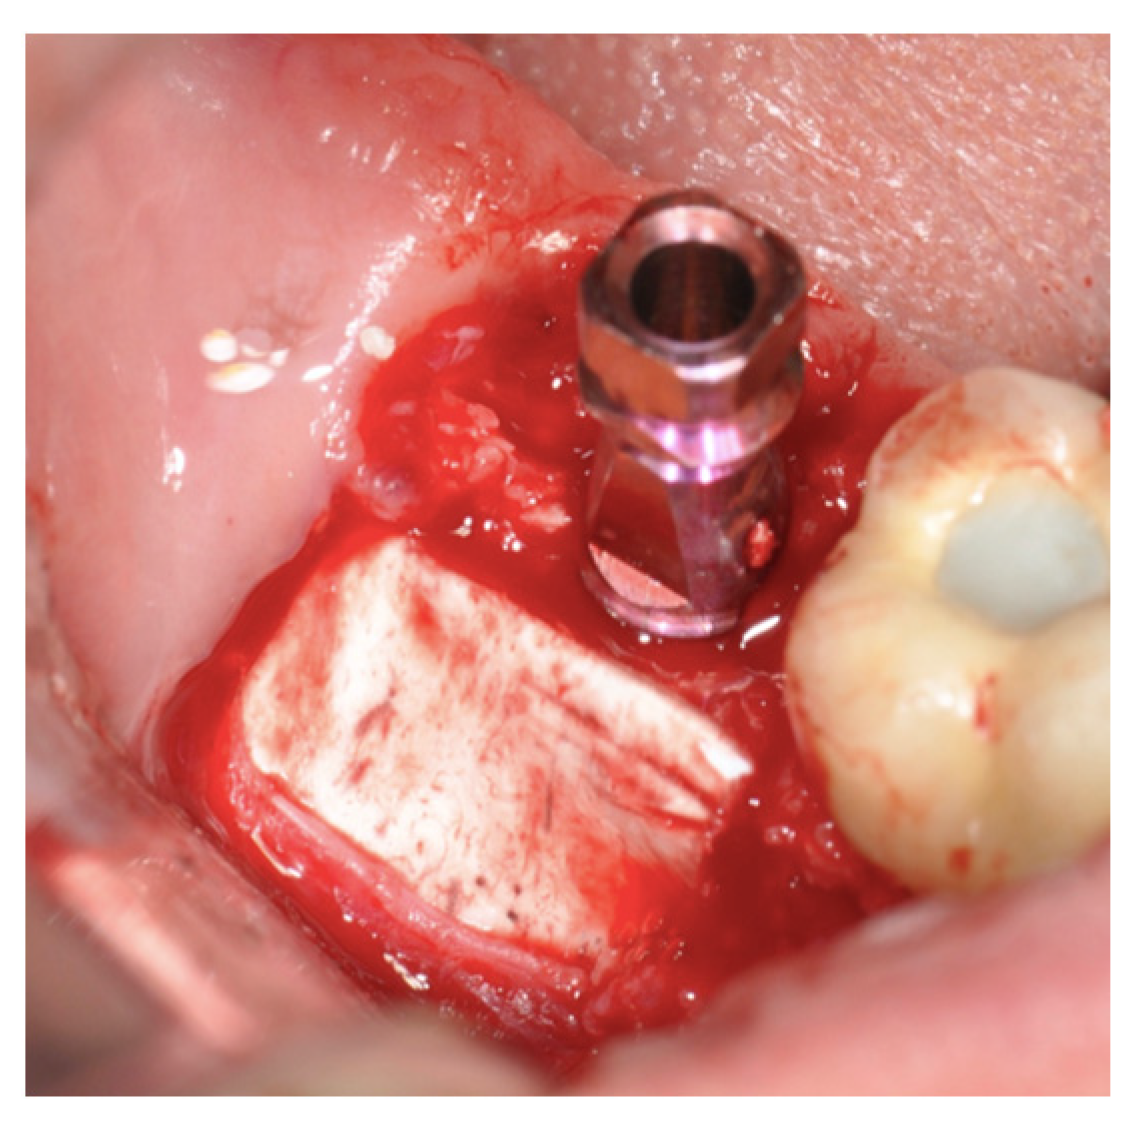

New Operative Protocol for Immediate Post-Extraction Implant in Lower-First-Molar Region with Rex-Blade Implants: A Case Series with 18 Months of Follow-Up

2.2. Surgical Technique